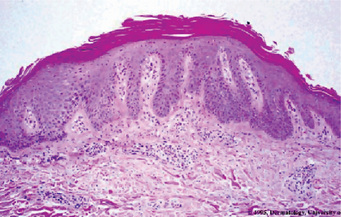

The microscopic appearance of psoriasis is characterized by uniform parakeratosis, absence of the stratum granulosum and elongation and clubbing of the rete pegs (Figs. 19-8, 19-9). The epithelium over the connective tissue papillae is thinned, and it is from these points that bleeding occurs when the scales are peeled off. Tortuous, dilated capillaries extending high in the papillae are prominent. Intraepithelial microabscesses (Monro's abscesses) are a common but not invariable finding; they are reported by Pisanty and Ship to be absent in oral psoriasis (Fig. 19-10). Mild lymphocytic and histiocytic infiltration of the connective tissue is also typical, particularly perivascular and periadnexal in location.

Histopathologic examination of lesional tissue is the most relevant investigation in cases of OLP. Typical findings include hyperparakeratosis or hyperorthokeratosis with thickening of the granular layer, acanthosis with intracellular edema of the spinous cells in some instances, the development of a ‘saw tooth’ appearance of the rete pegs. Band-like subepithelial mononuclear infiltrate consisting of T-cells and histiocytes; increased numbers of intraepithelial T-cells; and degenerating basal keratinocytes that form colloid (Civatte, hyaline, cytoid) bodies, which appear as homogenous eosinophilic globules are consistently seen.

Figure 19-5 Oral lichen planus.

(A) Note the basilar degeneration and band-like infiltration of inflammatory cells in the subepithelial zone. (B) Histopathology of lichenoid mucositis (H and E x 100). Note the diffuse infiltration of inflammatory cells involving parts of submucosa. (C) Photomicrograph of Langerhans cells in lichen planus (Gold Chloride staining x400). (D) Photomicrograph of Langerhans cells in lichenoid mucositis (Gold Chloride staining x400) Courtesy of the Dept of Oral Pathology, Ragas Dental College and Hospital, Chennai.